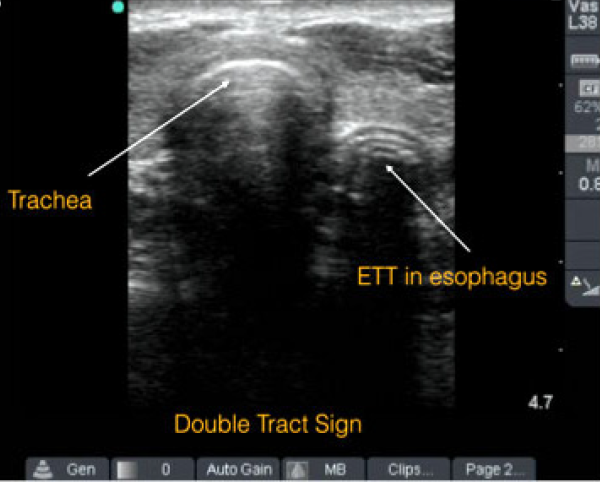

Using Point-of-Care Ultrasound to Confirm Endotracheal Tube Placement

Using Point-of-Care Ultrasound to Confirm

Endotracheal Tube Placement